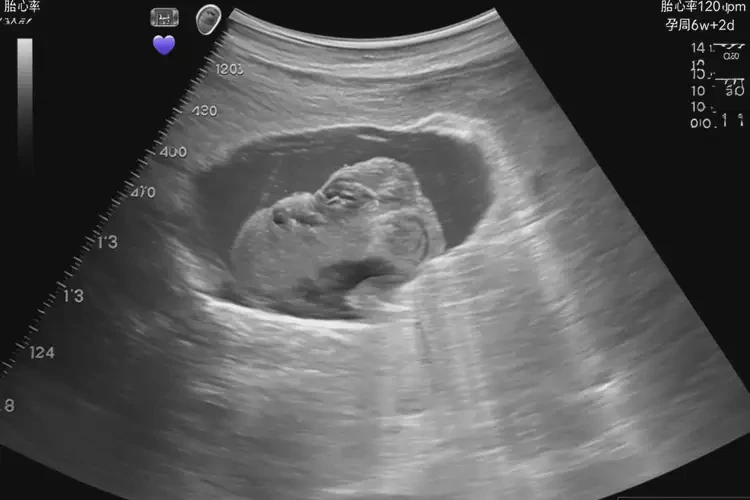

懷孕40多天胎心率85寶寶還能要嗎(圖1)

懷孕40多天胎心率85寶寶還能要嗎(圖2)

懷孕40多天胎心率85寶寶還能要嗎(圖3) 懷孕40多天胎心率85寶寶還能要嗎(圖4)